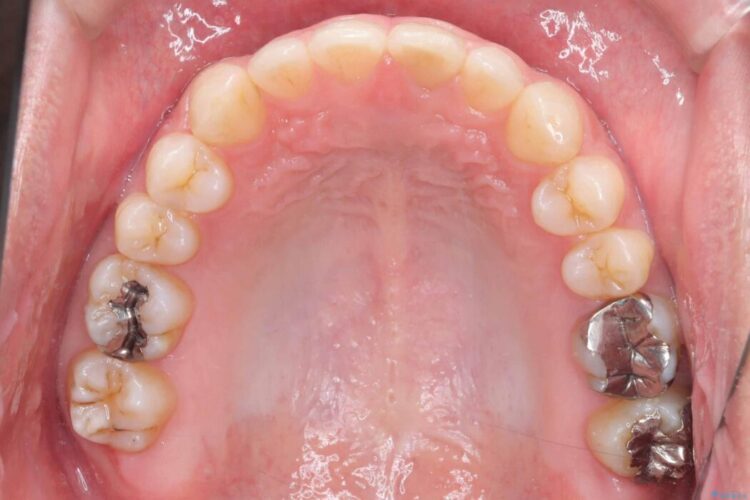

歯の隙間とデコボコ、シザーズバイトも改善され、咬み合わせや見た目が整い、患者様にも大変ご満足いただけました。